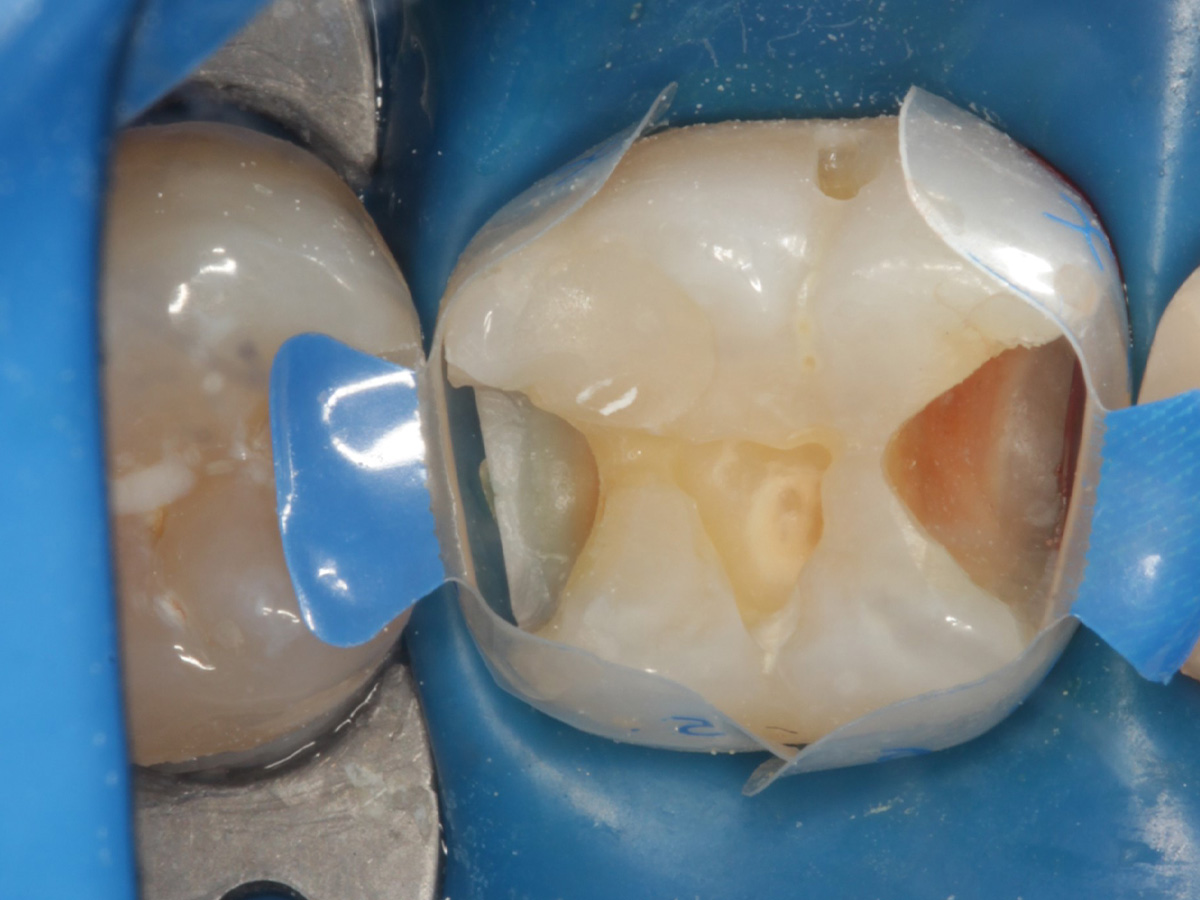

Abbildung 10

Height Indicator vor Auswahl der passenden Evolve Matrize distal

Abbildung 11

Height Indicator vor Auswahl der passenden Evolve Matrize mesial

Abbildung 12

Applikation der Matrizen: Evolve Blau Molar 5 mm distal und 6 mm mesial